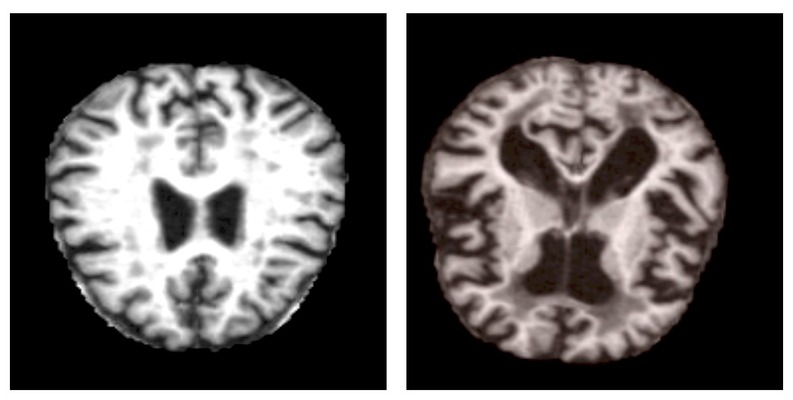

1.项目背景

阿尔茨海默病作为最常见的神经退行性疾病之一,早期诊断对延缓病情进展和提高患者生活质量具有重要意义。临床上,脑部磁共振成像(MRI)是评估脑结构变化、辅助诊断的重要工具,能够显示海马体萎缩、脑室扩大等与疾病相关的典型征象。然而,传统影像诊断依赖放射科医生的经验判断,不同医生之间可能存在解读差异,且早期病变的细微特征不易被肉眼准确识别。随着医疗影像数字化程度的提高,积累了大量患者MRI数据,如何利用这些影像资料实现客观、标准化的疾病评估成为研究热点。深度学习技术,特别是卷积神经网络,在医学图像分析领域展现出显著优势。这些模型能够从像素级数据中自动学习疾病的影像特征模式,不受主观经验影响,有望为阿尔茨海默病的早期识别提供新的技术支持。基于MRI图像的自动分类系统不仅可以辅助临床医生提高诊断效率和一致性,还能为疾病进展监测和疗效评估提供量化参考。

本项目核心技术采用基于Xception架构的迁移学习策略。Xception是一种高效的深度可分离卷积神经网络,通过将标准卷积分解为深度卷积和逐点卷积两个步骤,在保持较强特征提取能力的同时显著减少了模型参数量。这种设计使其特别适合处理医学图像这类需要精细特征分析的任务。我们以在ImageNet大型图像数据集上预训练的Xception模型为基础,保留其底层通用特征提取能力,替换顶部分类层并针对阿尔茨海默病四分类任务进行微调训练。结合全局平均池化、Dropout正则化以及自适应学习率调整等策略,构建了一个能够从脑部MRI图像中自动识别不同痴呆程度的分类模型,为临床辅助诊断提供了一种可行的技术路径。

本实验数据集来源于Kaggle,数据包括 MRI 图像。数据分为四类图像,既有训练图像,也有测试集:

- Mild Demented 轻度痴呆

- Moderate Demented 中度痴呆

- Non Demented 非痴呆

- Very Mild Demented 非常轻度的痴呆

数据包含两个文件夹。其中一个是增强版,另一个是原版。